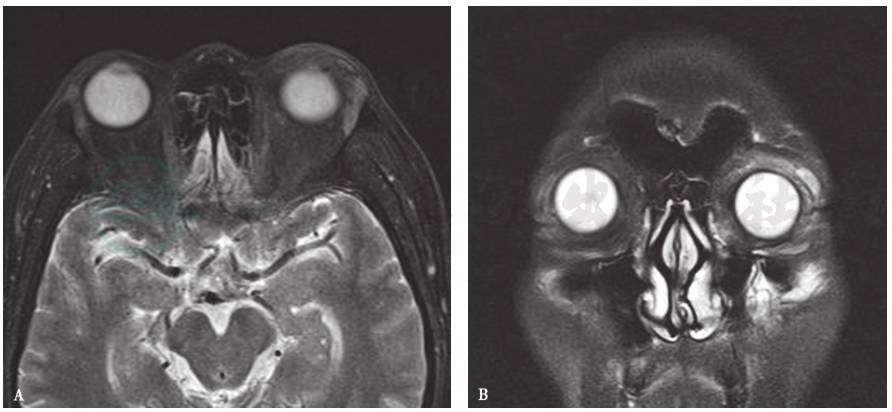

2.MRI表现

泪腺肿胀,T1WI呈等或高信号,T2WI呈稍高信号(图2),脂肪抑制T2WI呈高信号,信号不均匀。

图2左泪腺及眼睑外伤MRI检查

A、B.分别为横轴位、冠状位脂肪抑制T2WI图像:示左侧泪腺体积增大、呈高信号,左眼睑软组织增厚、信号增高一般很少见有单纯泪腺外伤,多为眼睑外伤、外上方眶缘骨折合并泪腺外伤。泪腺外伤X线平片不能显示。